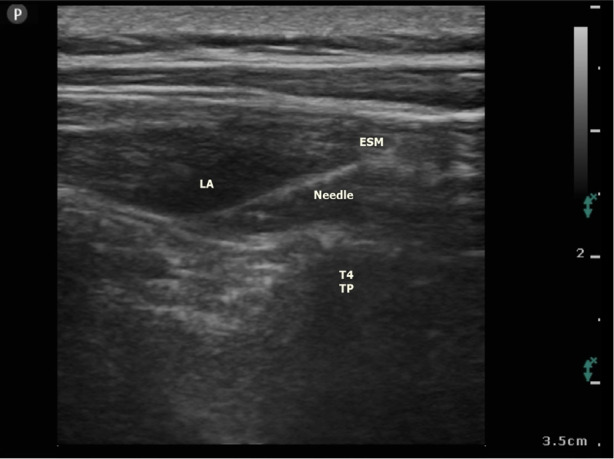

Objective: Analgesia management following breast surgery is a critical concern. The erector spinae plane block (ESPB) is a regional anaesthesia technique that is frequently used for analgesia after breast surgery. However, there is no consensus on the volume. Therefore, the aim of this study was to compare ESPB performed using 20 mL vs. 30 mL.

Methods: The study included 43 female patients with American Society of Anesthesiologist class I-II physical status. Participants were randomized into two groups: 20 mL ESPB and 30 mL ESPB. Ibuprofen (400 mg) 3x1 was ordered, and a fentanyl patient-controlled analgesia device was attached intravenously to the participants. If the pain score was ≥4, meperidine (0.5 mg kg-1) was administered.

Conclusion: A similar analgesic effect is achieved by performing ESPB using 20 or 30 mL of local anaesthetic at the same concentration.